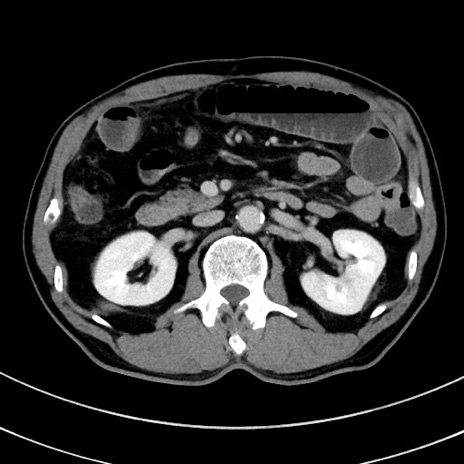

症例8(横断像)

【症例】 60歳代男性

【主訴】 黒色吐物

【現病歴】 4日前から嘔気自覚、2日前の朝食後にも嘔気あり、自分で手で嘔吐反射起こし嘔吐したところ血が混ざっていたため受診。

【既往歴】 5年前汎発性腹膜炎を伴う急性虫垂炎で手術、高血圧、前立腺肥大症、高脂血症

【身体所見】 腹部正中に手術癩痕あり 腹部平坦・軟圧痛なし膨満感あり

【データ】WBC 8400、CRP 4.54